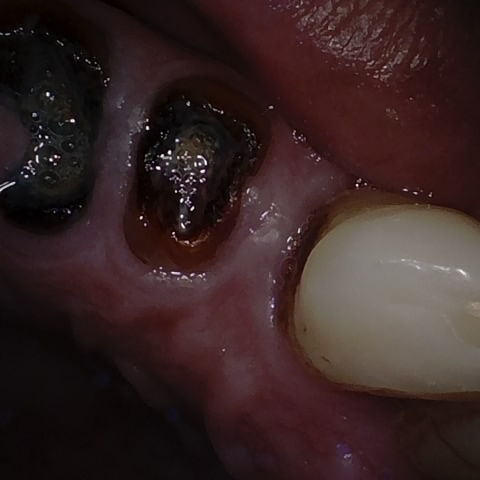

Annotated as "Good"